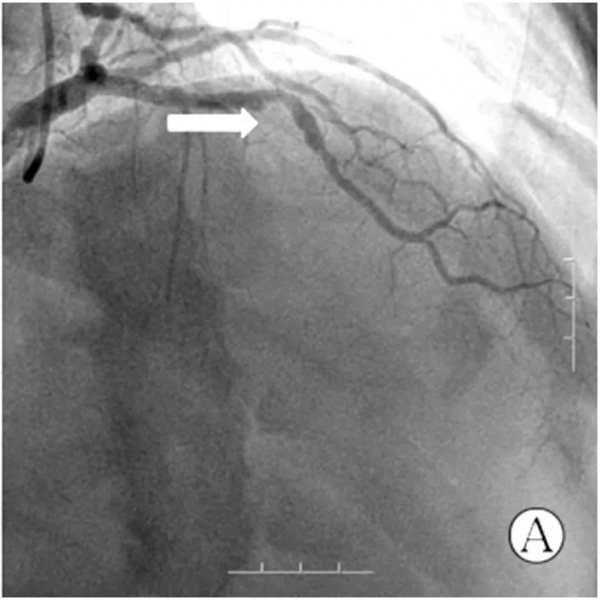

入院後即刻完善準備行急診冠狀動脈造影,顯示右優勢型冠狀動脈,前降支自中段第一對角支發出後100%閉塞,見圖2A;中間動脈近段侷限性狹窄50%,右冠狀動脈較粗大,第二轉折稍遠處侷限性狹窄95%,見圖2B。立即開通罪犯血管,經右側橈動脈入路,使用6F EBU3.5指引導管將BMW導絲順利透過閉塞段,常規預擴張後植入3 mm×18 mm支架一枚,並給予後擴張,即刻效果理想,見圖2C。此時患者一般狀況良好,生命體徵平穩,無任何不適症狀,考慮手術操作簡單,右冠狀動脈血管粗大且病變重,故一併處理,保留導絲並更換6 F JR4指引導管,仍使用BMW導絲並常規預擴張,順利植入4 mm×14 mm支架一枚,並給予後擴張,即刻效果理想,見圖2D;處理右冠狀動脈共使用3 min,造影劑10 ml,順利結束手術,術後給予水化治療及強化抗栓治療。

注:A 為前降支完全閉塞(箭頭所示),B 為右冠狀動脈重度狹窄(箭頭所示),C 為前降支被開通, D 為右冠狀動脈狹窄被解除

圖 2 患者冠狀動脈造影及 PCI 影象